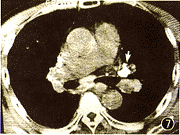

煤工塵肺2.X線檢查煤工塵肺胸片表現特徵有:網狀改變;結節狀改變;結節融合;塊狀陰影和多量絨毛狀改變。網狀改變被認為是煤工塵肺最早的表現,在肺野呈現瀰漫性細網狀陰影。而此時在臨床上無任何症狀。隨著結節的擴展,病變融合成不透明的進行性大塊纖維化,通常位於兩肺上野,也可跨肺葉融合至中、下肺野,有時僅發生在一側肺野,通常為大塊狀,均勻的、界限明顯的陰影。這些改變往往在單純性煤工塵肺彌散結節陰影的背景上發生。